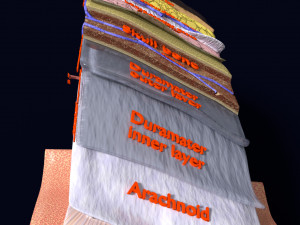

A blend model of brain along with its covering layers (meninges), skull bone and scalp labelled in detail and anatomically precise. The parts depicted are white, gray, pia, arachnoid, dura, bone, skin, fat, aponeurosis, periosteum, falx cerebri and more.

The material is high resolution image textures and normal maps based on non overlapping UVs. The texture and normal maps are packed with the blend file itself.